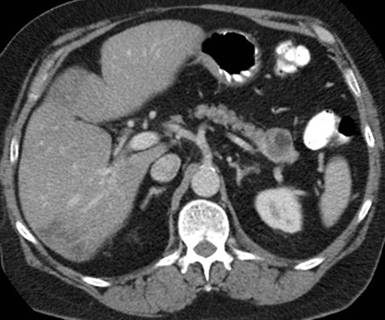

A 58-year-old man initially presented to the Urology team in 2008 with left sided abdominal pain presumed to be renal colic. A CT of his abdomen excluded renal calculi but revealed an incidental 3.5 cm complex cyst in the tail of his pancreas (Figure 1).

Figure 1. Initial CT image of the an incidental 3.5 cm complex cyst in the pancreatic tail proven to be lymphoepithelial cyst in 2008. |